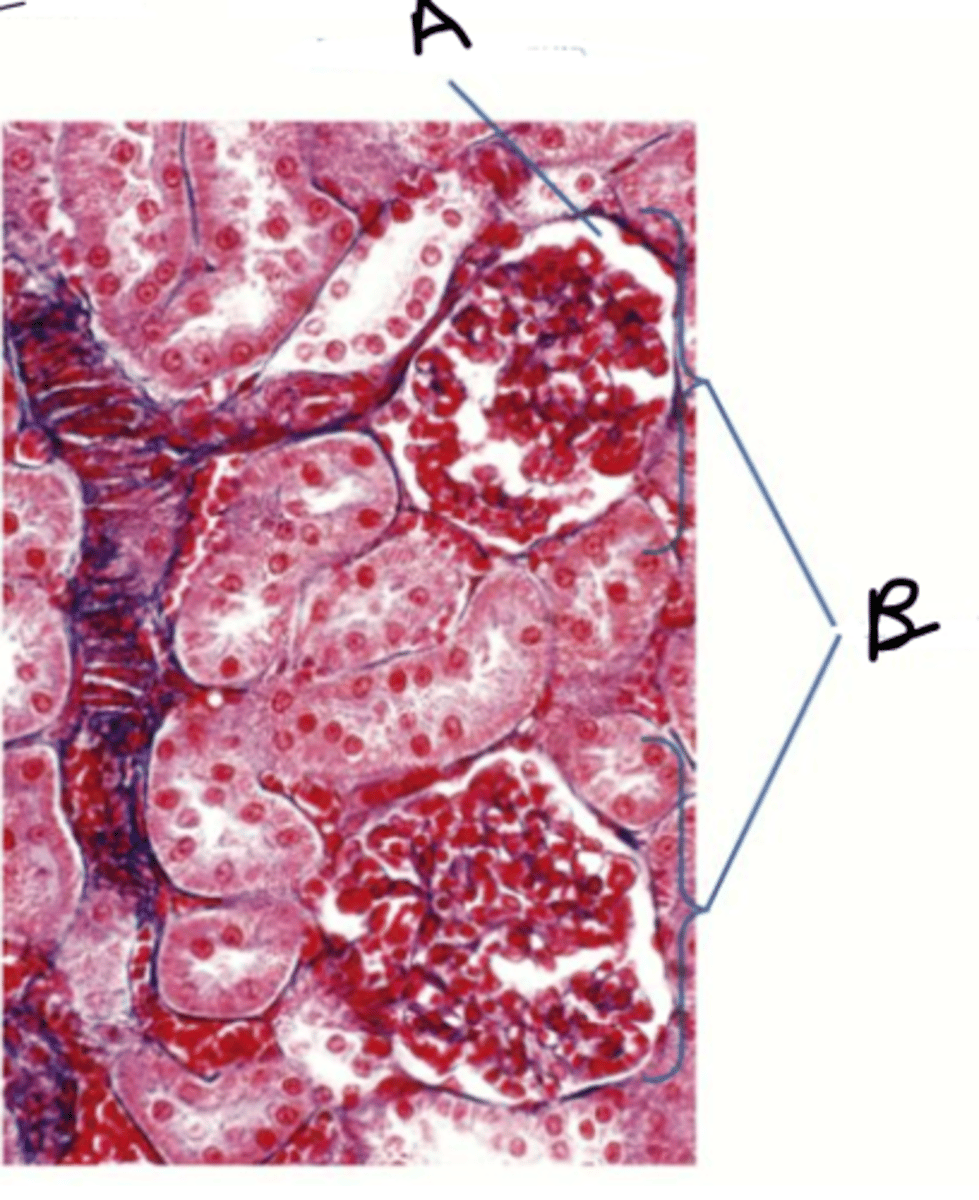

A - glomerulus

B - bowman's capsule

name A & B

A - bowmans capsule

B - glomeruli

how do you distinguish between the PCT and DCT under a microscope?

PCT will have microvilli whereas DCT will not